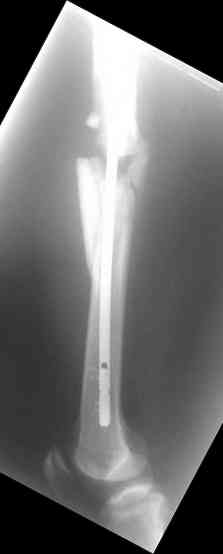

одна проблема в моей компьютерной неграмотности(не смог прикрепить снимки), а другая в том, что связь с пациентом потеряна и,насколько я понял в своем регионе ему посоветоваться не с кем, кроме главного врача который отреагировал на выбранную нами тактику так: "там тебя использовали в качестве подопытного кролика...".

Надеюсь сейчас показать перелом, а потом синтез.